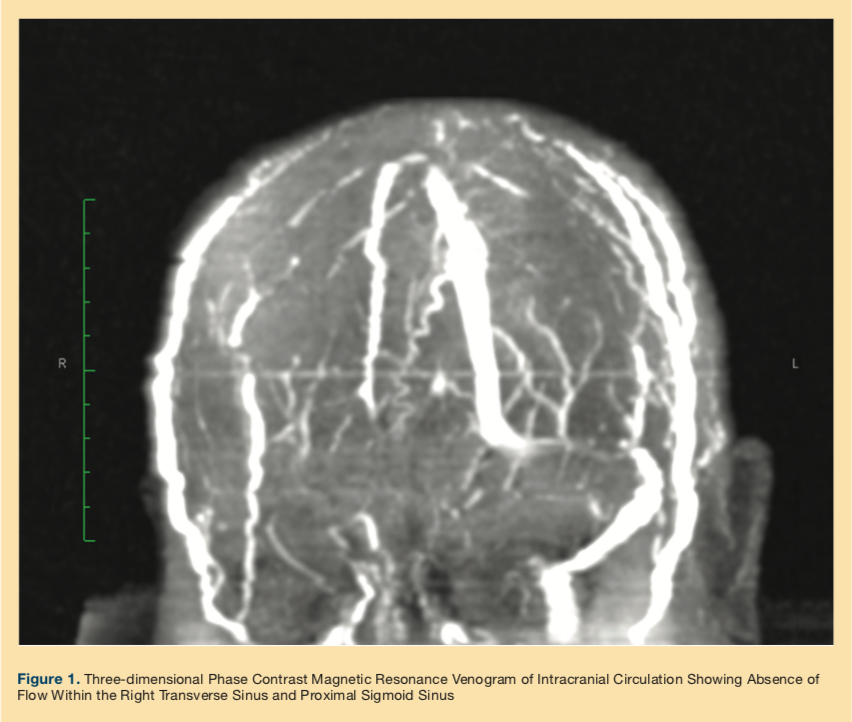

The patient continued to experience intractable headache and hyperalgesia on the left side of her head, raising concerns for a giant cell arteritis (GCA); however, she lacked other typical features of GCA. Neurology was consulted, and further workup with CT angiogram showed a filling defect in the right transverse and sigmoid sinus. A subsequent three-dimensional phase magnetic resonance venogram (MRV) of the brain (Figure 1) confirmed the diagnosis of CVST, and immediate anticoagulation with unfractionated heparin was started.